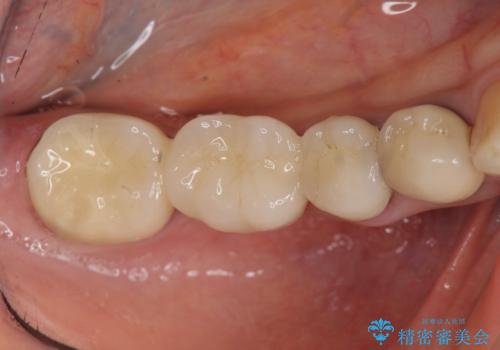

臼歯部メタルフリー再補綴

- 110万円(仮歯×8・ファイバーコア×6・ジルコニアクラウン×8)費用は治療当時の料金となります

装着して長期間経過したブリッジやクラウンは隙間から細菌が侵入し虫歯が再発してしまっていることがあります。

長期的に問題のないブリッジ・クラウンを作製するため、虫歯をしっかりと除去すること精密な根管治療を行うことが肝要です。